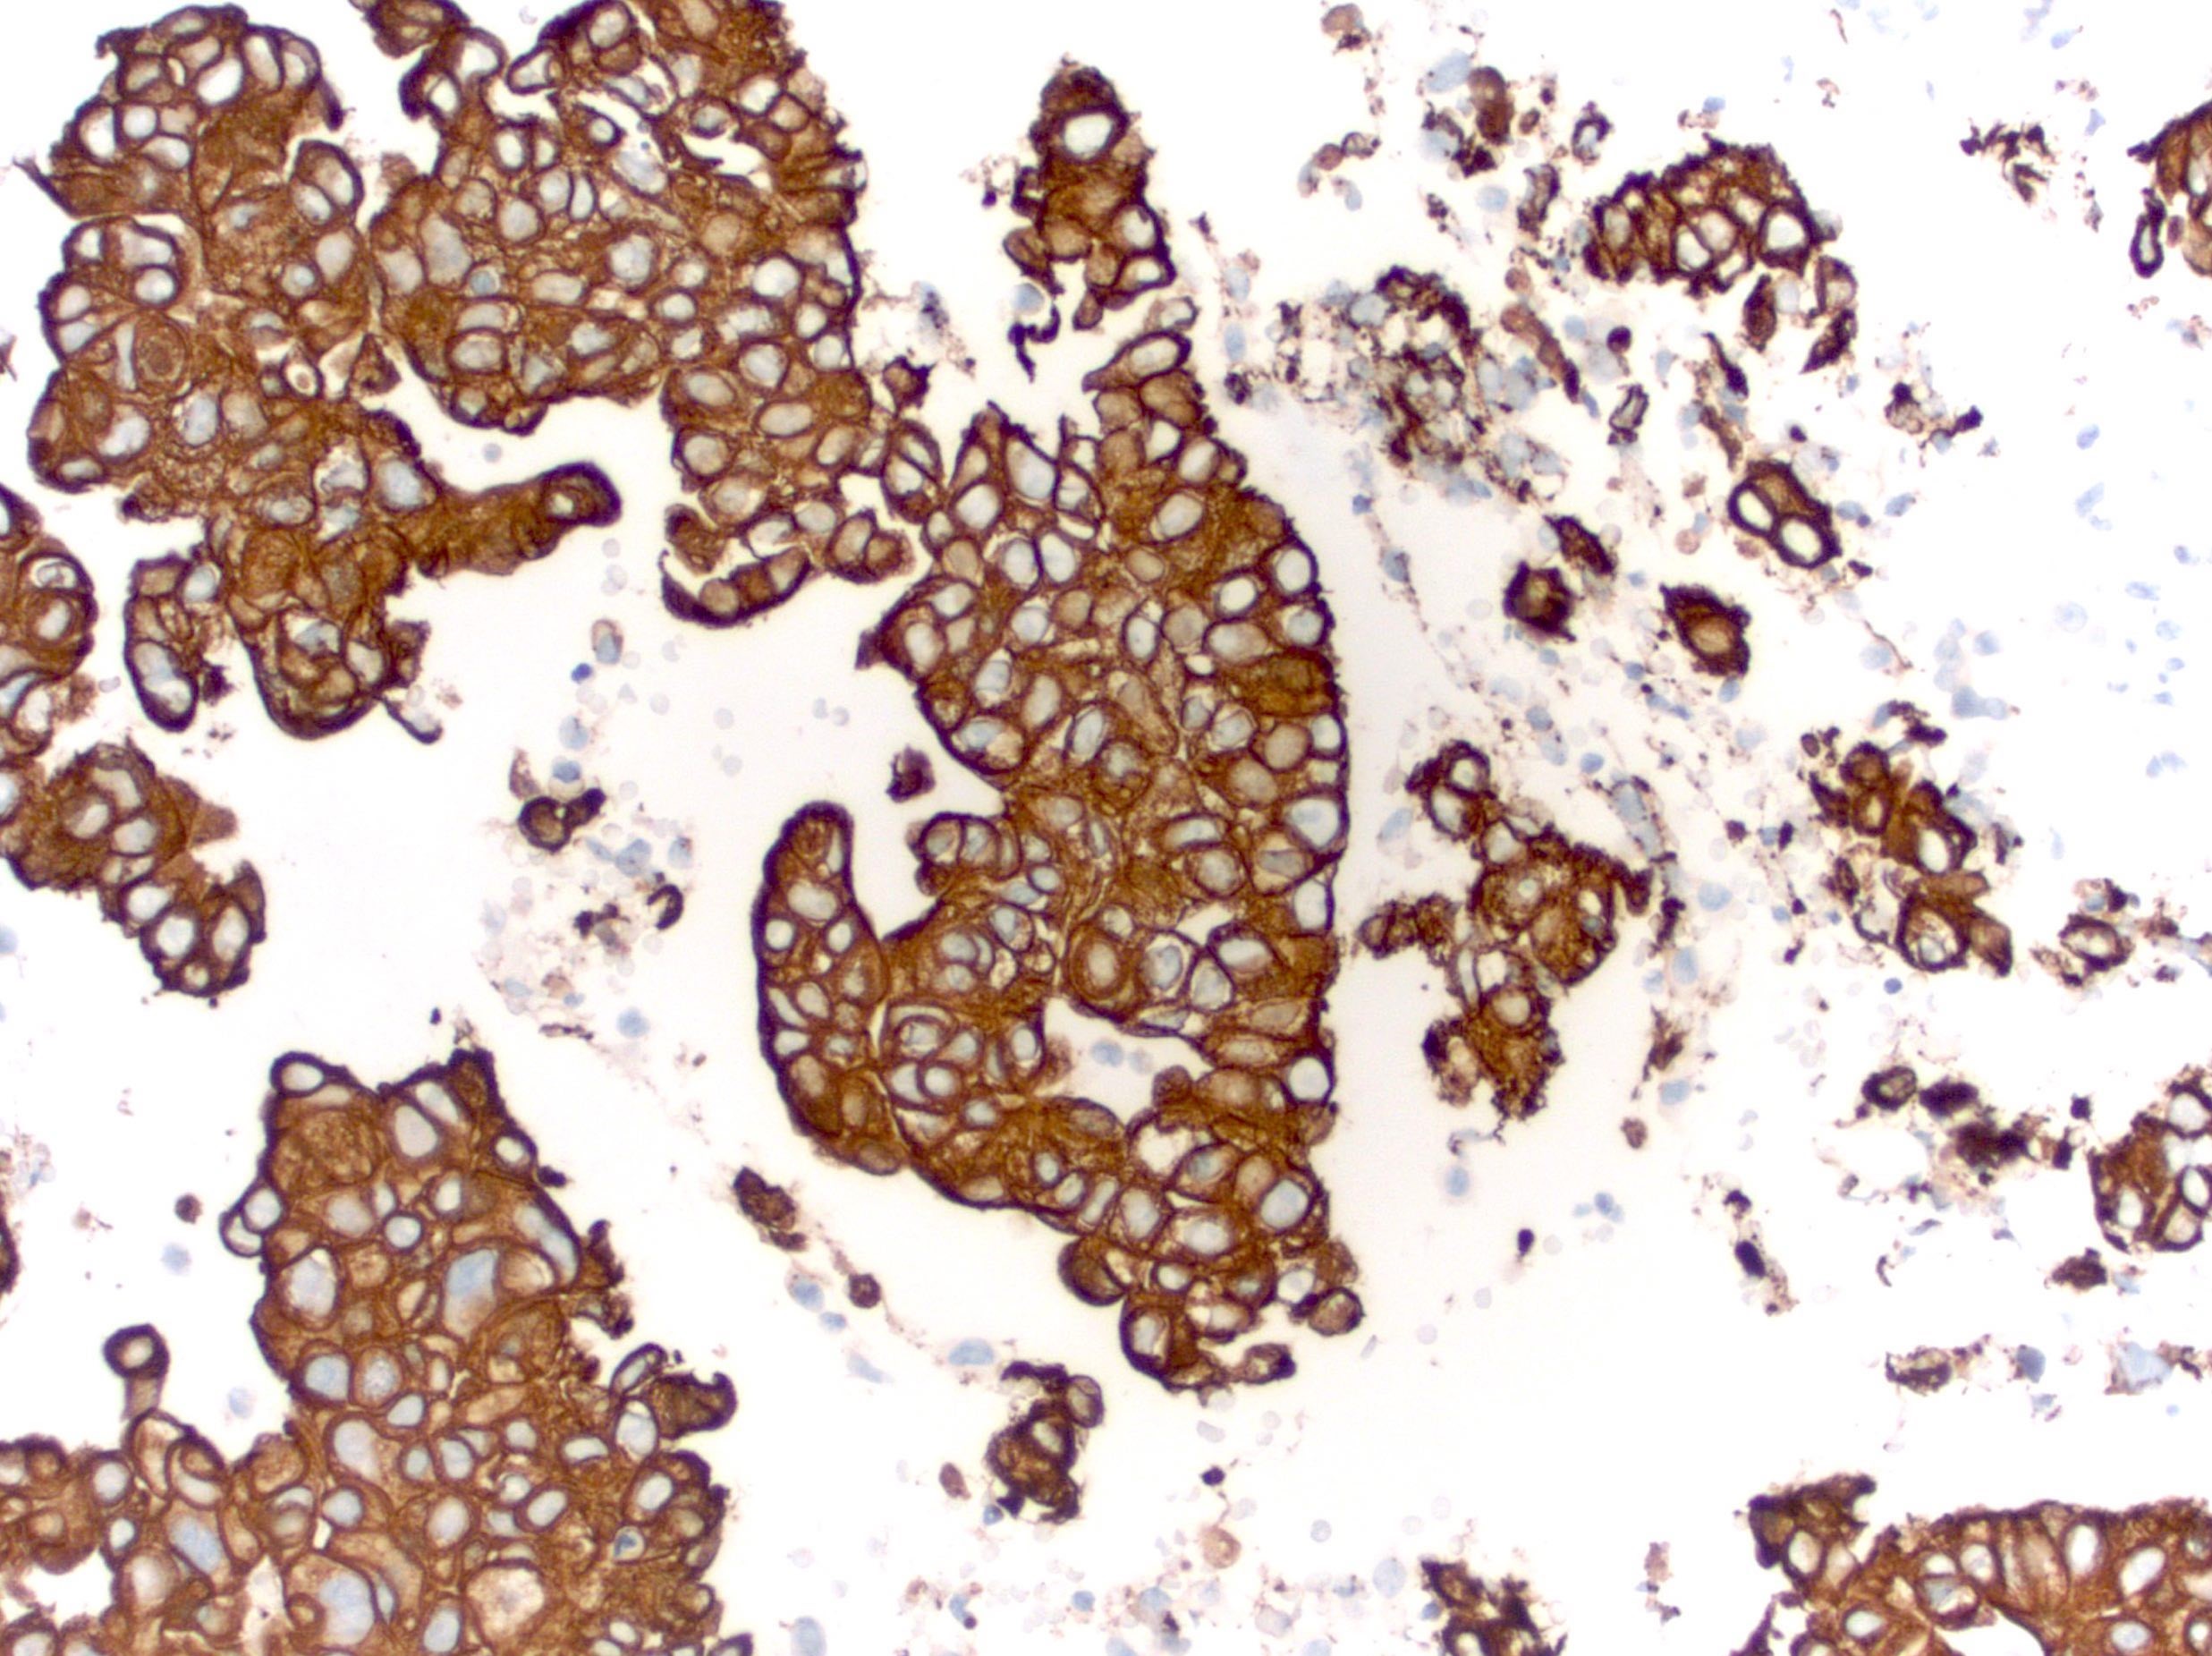

Microscopic (histologic) images

Contributed by Emily S. Reisenbichler, M.D., Andrey Bychkov, M.D., Ph.D., Maria Tretiakova, M.D., Ph.D. and Debra Zynger, M.D.

Positive staining - tumors

- Primary and metastatic urothelial carcinoma (67 - 93%) (Am J Surg Pathol 2007;31:673, Am J Surg Pathol 2013;37:1876)